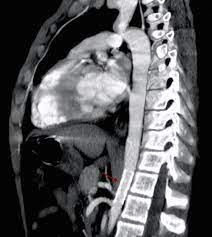

Pronostico en pacientes con coartación aórtica

La coartación aórtica, si no se trata, puede llevar al desarrollo de insuficiencia cardíaca, especialmente en lactantes y personas de mayor edad. La insuficiencia cardíaca ocurre cuando el corazón no…

Tratamiento de la coartación aórtica

El tratamiento de la coartación aórtica es necesario debido a las posibles complicaciones y consecuencias negativas que puede causar esta afección en la salud de una persona: Prevenir la progresión…